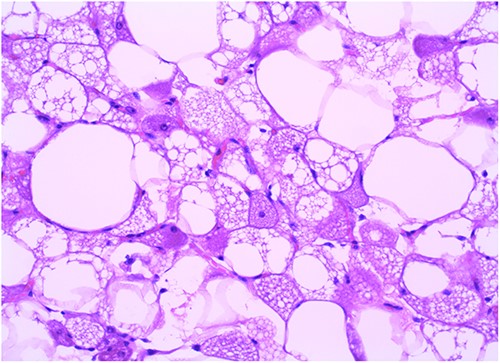

A 32-year-old female presented to the clinic with a palpable soft tissue back mass noticed a month prior to her visit. The patient had not noticed any change in size. On physical examination, a minimally mobile painless soft tissue mass was palpated and located on the left side of the back. No skin changes were noted. The mass was ~13 × 15 cm on palpation. No punctate, drainage nor erythema were noted. The mass was not attached to the skin. Ultrasound was performed 20 days prior to her visit and detailed a large soft tissue mass at the site of clinical concern in the patient’s back on the left side measuring 10.5 × 8.5 × 3.3 cm. Ultrasound-guided core biopsy was performed under local anesthetic in the office setting and demonstrated a Lobulated tumor composed of a mixture of cell types in varying proportions with small, bland, central nuclei, polygonal cells with granular eosinophilic cytoplasm and multivacuolated cells with numerous lipid droplets. Some univacuolated adipocytes were identified. Medium-sized prominent stromal vessels were noticed. Mitotic figures were rare. A computed tomography (CT) scan of chest with contrast was performed to estimate the relationship of the mass to adjacent anatomical structures. The CT scan showed 12.6 × 10 × 3.9 cm lipomatous mass beneath the latissimus dorsi muscle along posterolateral aspect of upper abdomen/lower thorax favoring an intramuscular lipoma (Fig. 3). Patient agreed to have complete excision of the mass. After excision in the operating room, the specimen was sent to pathology and showed a well-circumscribed 266 gm fatty mass that was serially sectioned revealing homogenous yellow adipose tissue on cut section (Fig. 2). The specimen was submitted per grossing protocol which is one section per 1 cm. Final pathology confirmed diagnosis of hibernoma (Fig. 1).

In the emergency department, vital signs were remarkable for elevated blood pressure of 166/81, but otherwise stable and afebrile. WBC count was elevated at 15.4 with left shift and hemoglobin was low at 9.6. Complete Metabolic Panel was notable for hyponatremia of 128, and mildly elevated BUN/serum creatinine of 26/1.5 which was slightly higher than his baseline of 17/1.3. Liver function tests were unremarkable. UA showed likely UTI with positive esterase, high RBC/WBC and bacteria and protein. A CT of the abdomen and pelvis was done, showing a left non-obstructing kidney stone and a left retroperitoneal fat density with stranding along the left iliopsoas measuring 12.6 × 8.1 cm × 3.7 cm, which was described as possibly a part of infectious or malignant process (Fig. 5). Subsequently, patient’s prior CT scans were available to be reviewed and it showed the same lipomatous mass 9 years earlier. (Fig. 6). Given the patient’s symptoms of left lower extremity pain and the possibility that the mass was responsible, a CT-guided core biopsy was ordered for diagnosis to rule out a malignant process as operative intervention was being contemplated. Pathology report of the core biopsy showed lobules of univacuolated adipocytes divided by thin septa. There were frequent multivacuolated adipocytes with small round nuclei, reminiscent of brown fat cells. No enlarged hyperchromatic cells, mitotic figures nor necrosis are seen. The findings supported the diagnosis of the lipoma variant of hibernoma (Fig. 4). Given the chronicity of the mass, the near identical size over 9 years and the diagnosis made from core biopsy, it was determined that the hibernoma was not the likely source of the patient’s LLE pain and hence the mass was not excised.

The diagnostic criteria for hibernomas include a circumscribed, lobulated, grossly yellow-brown mass with cellular features of brown fat, including numerous small cytoplasmic vacuoles and eosinophilic granular cytoplasm [6, 9]. Hibernomas are polygonal cytologically bland cells with small and central nuclei, prominent nucleoli, with rare cytologic atypia and mitotic figures [6]. The conventional lipoma in contrast to hibernomas are tumors with differentiation toward white fat cells [12]. The lipoma-like hibernoma variant has copious amounts of univacuolated cells mixed with scattered few granular multivacuolated hibernoma brown fat-like cells [8].